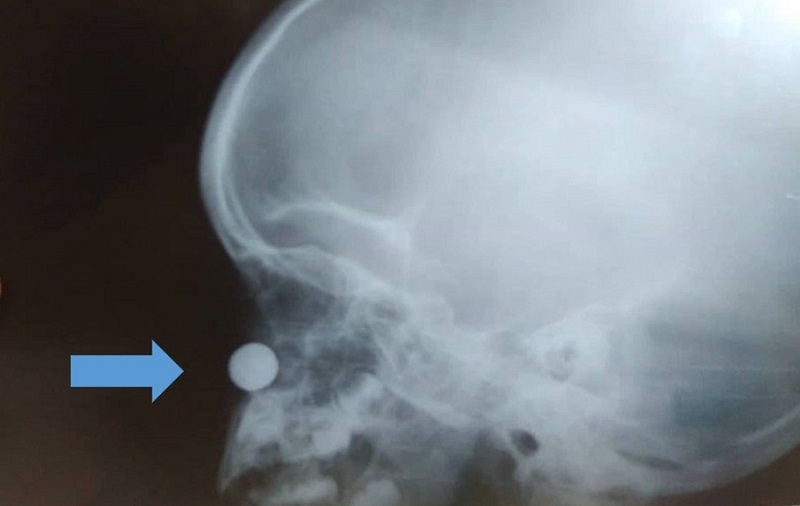

A criança foi levada para o Hospital Municipal de Medeiros Neto onde fez um raio x para localizar a bateria na narina. De lá o menino foi encaminhado para a Unidade Municipal Materno Infantil (UMMI), em Teixeira de Freitas. A secretaria da Saúde de Medeiros Neto providenciou uma ambulância para o deslocamento imediato.

Após a retirada da bateria a criança ainda fez dois raio-x na UMMI para averiguar se havia outro corpo estranho na narina, antes da alta médica.